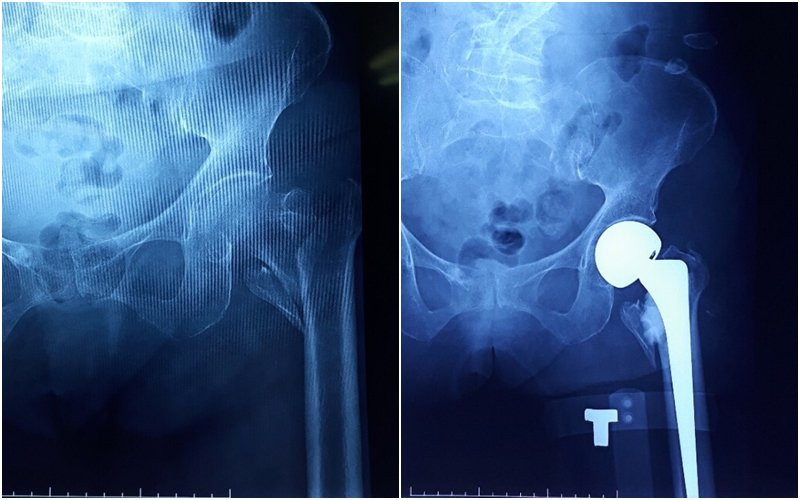

Kết quả chụp X-Quang cho thấy cụ B. bị gãy liên mấu chuyển xương đùi trái và được chỉ định mổ thay khớp háng nhân tạo. Tuy nhiên theo các bác sĩ, nguy cơ xảy ra rủi ro trong và sau phẫu thuật rất cao, do cụ B sức khỏe yếu và đã cao tuổi.

Khớp háng nhân tạo của bệnh nhân 102 được thay thành công